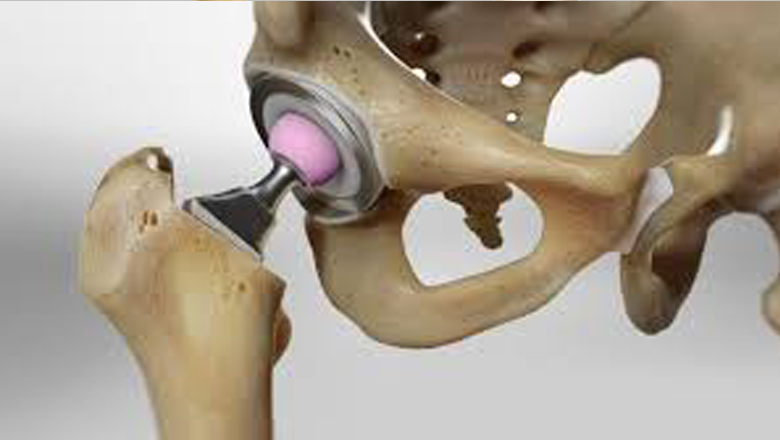

Hip Replacement Surgery (THR)

We offer Total Hip Replacement (THR) for patients dealing with severe hip problems, with a focus on relieving pain and improving everyday movement.

Conditions Treated:

- Avascular necrosis (AVN)

- Hip joint damage